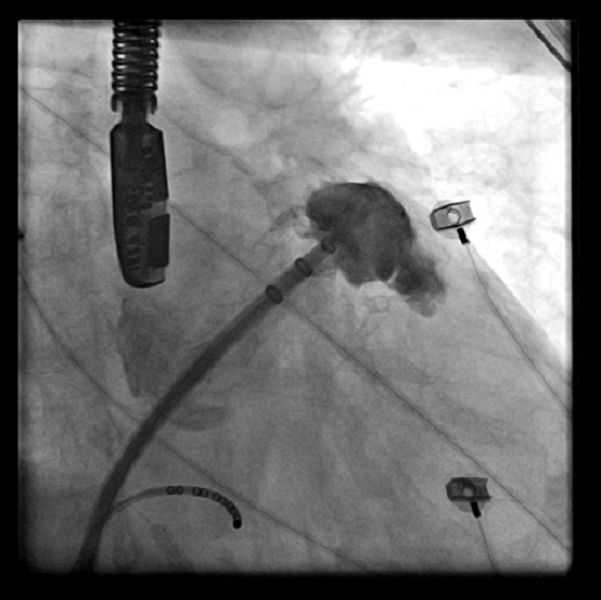

另一方面,左心耳是左心房內容易產生血栓的囊狀結構,約九成血栓都源於此處。透過左心耳封堵術,植入栓塞裝置將其「封閉」,便能有效阻斷血栓生成途徑。根據臨床觀察,術後可降低高達八成的中風風險,尤其對無法長期使用抗凝血劑或在用藥期間發生中風的病人,是重要的治療選擇。